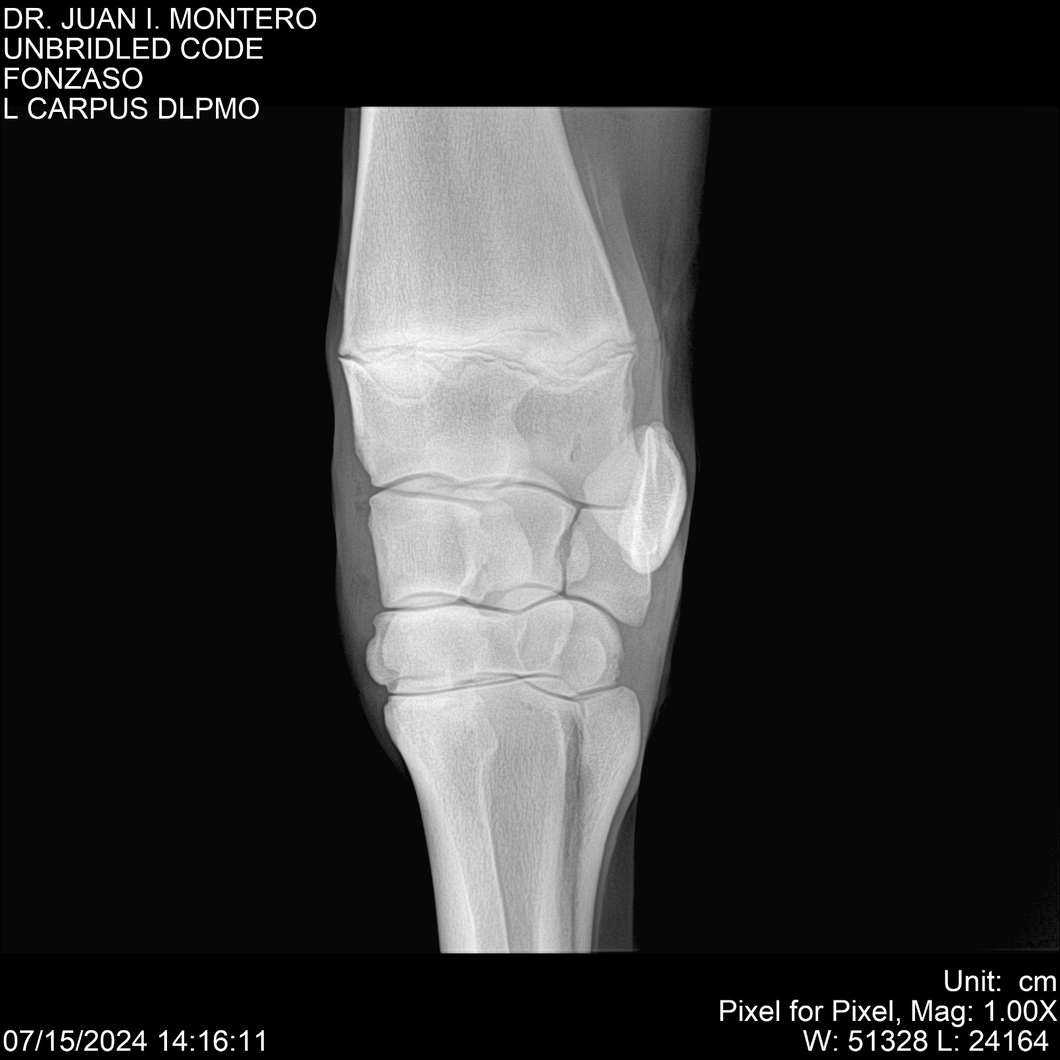

• Empresa: Abelenda N. R., Walter Hugo